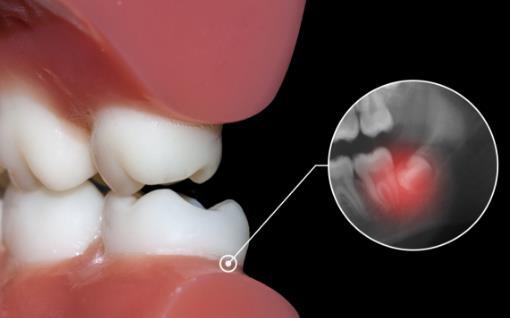

2.侵犯鄰牙:通常患者不自知,而由牙醫(yī)以X光診斷得知。通常智齒萌發(fā)的空間不足,而會倒在第二大臼齒上,因而造成第二大臼齒清潔不易,甚至是牙齒部分吸收的現(xiàn)象,造成患者不舒適或牙疼。

6.阻生齒:通常這是最討厭的一種,牙醫(yī)會覺得很難搞定,但病人卻不一定有感覺,因此忽略了。這一種類型的牙齒,通常埋在齒槽骨的里面,如果會痛,或是診斷會有病灶發(fā)生的時(shí)候,就需要拔除了。